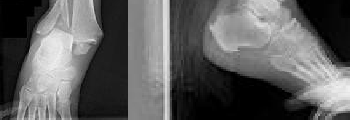

A 71-year-old man with long-standing ankle arthrosis who has previously had a subtalar fusion (Figure 42).

- Total ankle arthroplasty (TAA)_